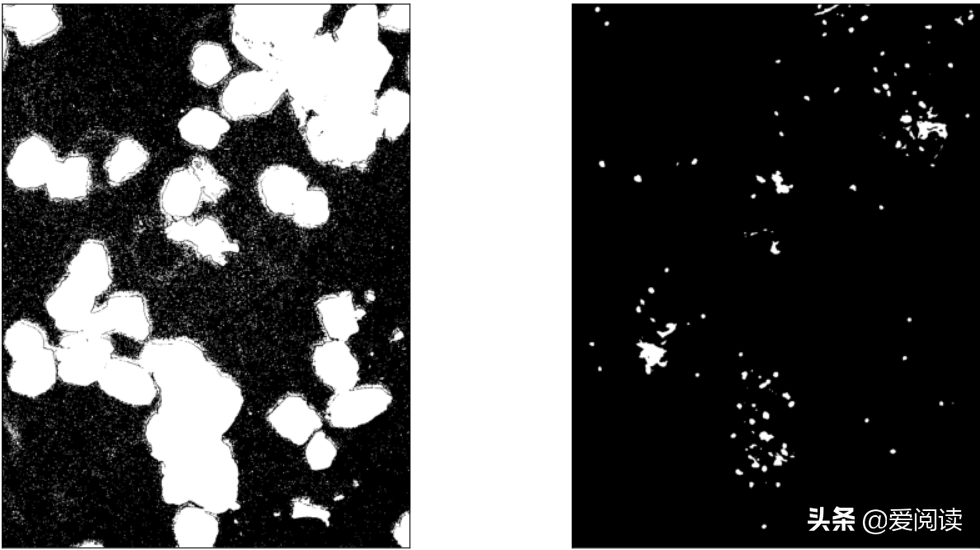

fig = plt.figure(figsize=(15,8))

plt.subplot(131), plt.imshow(bw_cell, 'gray'), plt.xticks([]), plt.yticks([])

plt.subplot(132), plt.imshow(bw_cell1, 'gray'), plt.xticks([]), plt.yticks([])

plt.subplot(133), plt.imshow(bw_cell2, 'gray'), plt.xticks([]), plt.yticks([])

plt.show()

你试过吗?图像(细胞)分割

区域分离: